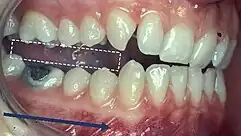

Incisor and molar classification

Classification of occlusion and malocclusion plays an important role in diagnosis and treatment planning in orthodontics. In order to describe the relationship of the maxillary molars to the mandibular molars, the Angle’s classification of malocclusion has commonly been used for many years.[8] This system has also been adapted in an attempt to classify the relationship between the incisors of the two arches.[9]

When describing the relationship between maxillary and mandibular incisors, the following categories make up Angle's incisal relationship classification:

- Class I: Mandibular incisors contact the maxillary incisors in the middle third or on the cingulum of the palatal surface

- Class II: Mandibular incisors contact the maxillary incisors on the palatal surface, in the gingival third or posterior to the cingulum. This class may be further subdivided into division I and division II:

- Class III: Mandibular incisors occlude with the maxillary incisors on the palatal surface, in the incisal third specifically or anterior to the cingulum

- In some cases the overjet is reversed (<0mm) and the mandibular incisors lie anterior to the maxillary incisors

Molar Relationship

When discussing the occlusion of the posterior teeth, the classification refers to the first molars and may be divided into three categories:

- Class I: The mandibular first molar occludes mesially to the maxillary first molar, with the mesiobuccal cusp of maxillary first molar occluding in the buccal groove of mandibular first molar

- Class II: The mesiobuccal cusp of the maxillary first molar occludes anterior to the buccal groove of the mandibular first molar

- Class III: If the mesiobuccal cusp of the maxillary first molar occludes posterior to the buccal groove of the mandibular first molar[8]

Any deviation from the normal relation of teeth (Class I) is considered a malocclusion.

Class I relationships are thought to be “ideal”, however this classification does not take into consideration the positions of the two TMJ’s. Class II and III molar and incisor relationships are thought to be forms of malocclusion, however not all of these are severe enough to require orthodontic treatment. The Index of Orthodontic Treatment Need is a system that attempts to rank malocclusions in terms of significance of various occlusal traits and perceived aesthetic impairment.[11] The index identifies those who would benefit most from orthodontic treatment and onward referral to an orthodontist.